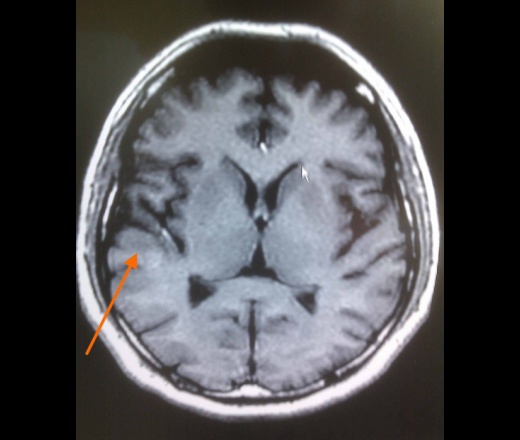

ID:53441

Подводник в каком смысле? Может проявления кессонной болезни? Не видел ни разу, но в принципе...

Сказал, что плавал на подводной лодке

Может быть , очаговые проявления на фоне иммунодефицита , а здоровьем пышет до поры до времени

Не может быть РС? Очаги юкстакортикальные.

РС не не похоже. Мне кажется здесь однозначно на контраст вводить. Может инфекция цнс? Паразитарная например цистицеркоз ? А где он путешествовал?

Неплохо бы законтрастировать. По отдельности кажда зона может тянуть на очаг постишемической природы, все вместе в разных бассейнах - как-то сомнительно. А на контрасте и паразиты могут быть видны и туберкулёзные гранулёмы, да хоть и активные очаги РС (хотя сомневаюсь, что это он).

Церебральный токсоплазмоз может быть?

Один очаг (в виске) умеренно и равномерно накопил контраст... Новых очагов при контрастировании не выявилось.

По поводу "подводника" - плавал на подводной лодне, несколько раз были аварийные резкие всплытия.

Вообще-то, похоже на демиелинизацию. А что другие отделы мозга - больше нет нигде?

Да, похоже на демиелинизацию, по почему локализация такая и с чем она связана? Больше нигде никаких очагов, базальные ядра без очагов...